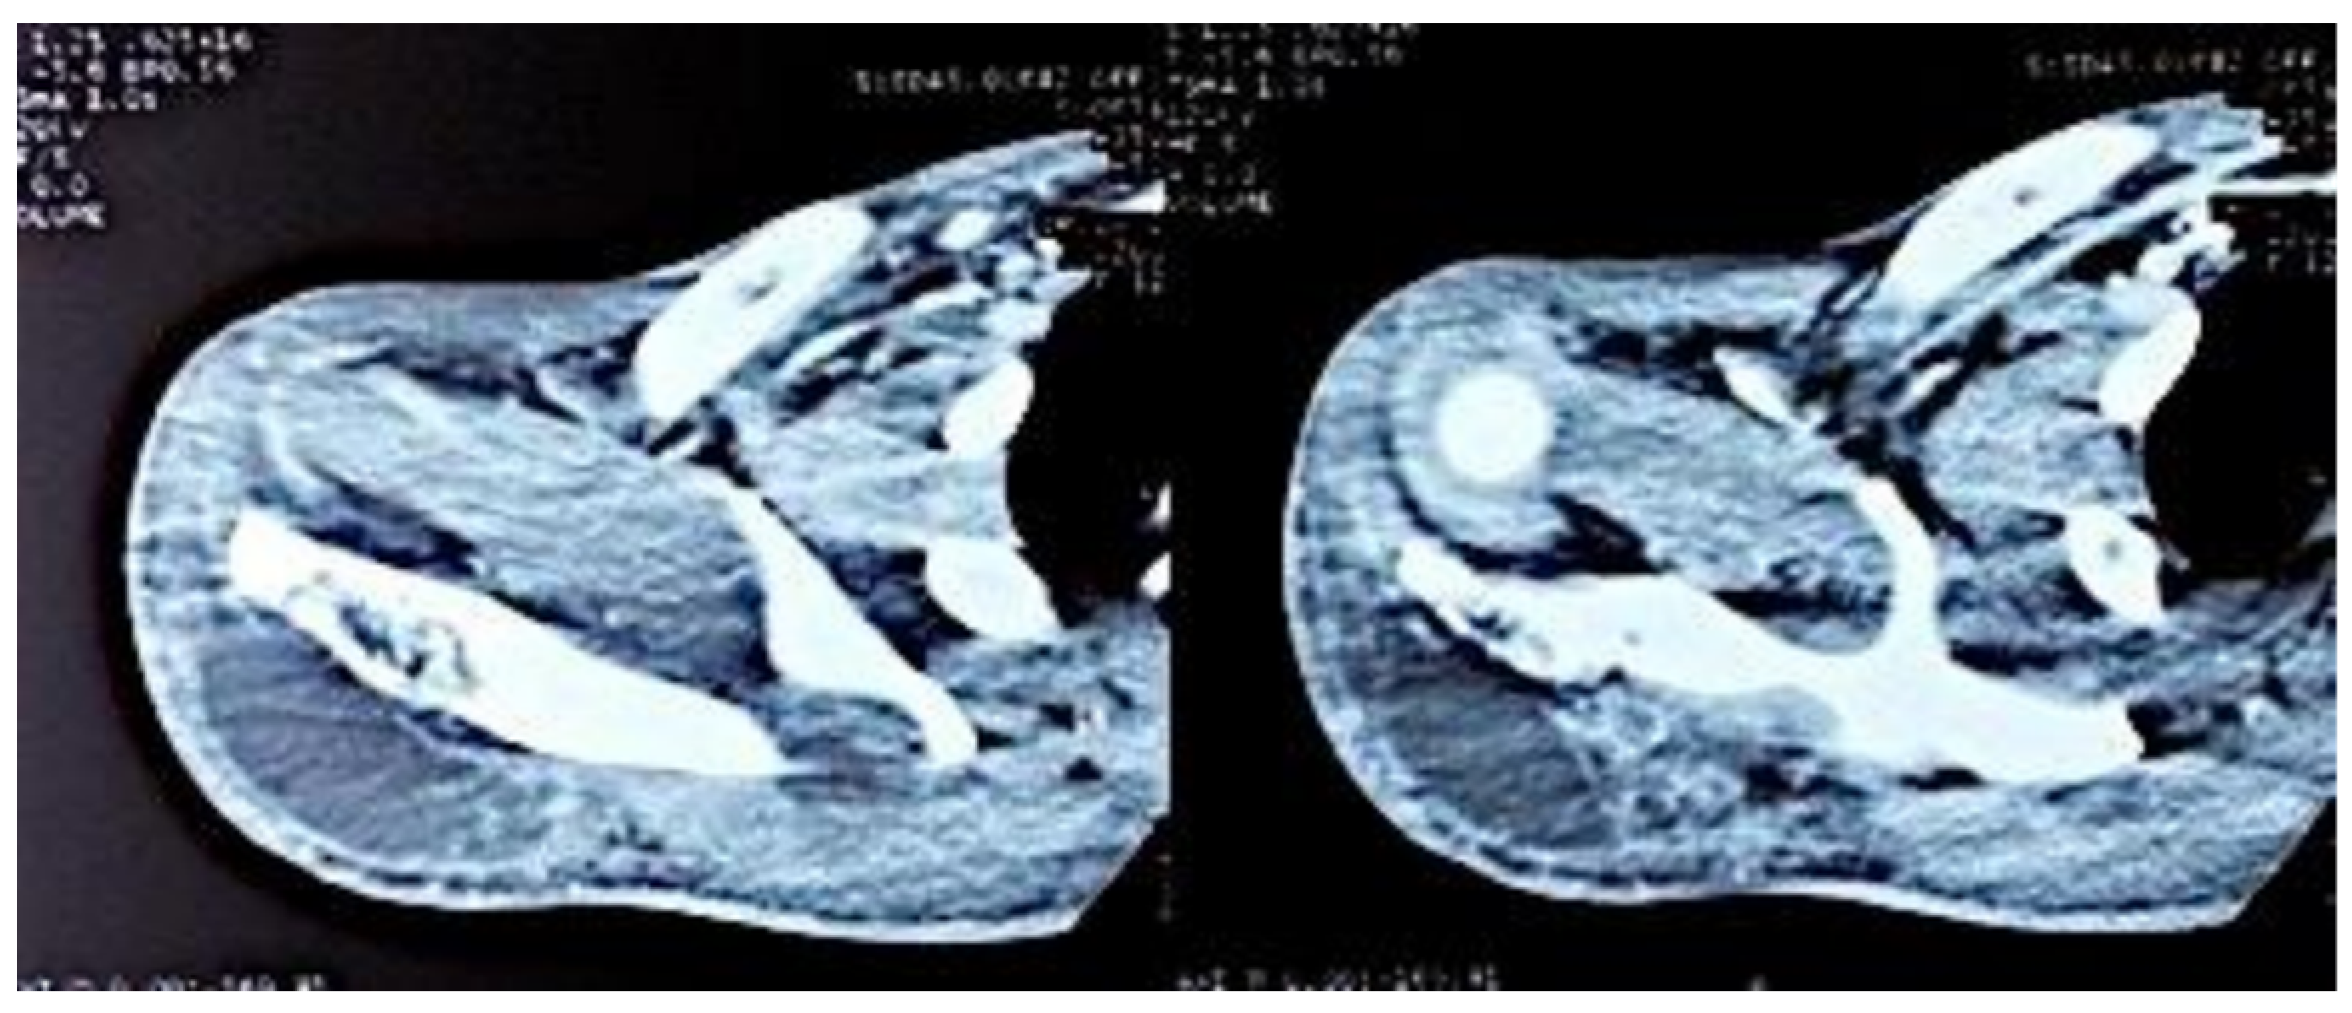

Figure 3. Axial CT sections of the shoulder, showing the lytic lesion of the distal ½ of the right scapular spine.

Figure 4. Axial sections of the shoulder CT scan, showing the deltoid collection.

Computed tomography of the right shoulder showed a lytic lesion of the right scapula with cortical rupture associated with scapular osteomyelitis (Figure 3, Figure 4 and Figure 5). The lesion was complicated by a deltoid abscess measuring 75 × 29 mm and extending over 105 mm (Figure 4), without joint effusion.

Clinically, osteoarticular TB can mimic other inflammatory and neoplastic bone lesions such as pyogenic osteomyelitis, fungal infection, multiple myeloma and metastatic disease [8]. For our case, the presence of any other germ was ruled out by pus culture and even multiplex PCR. The radiological features of skeletal TB are not specific. They may vary from lytic lesions and periarticular osteoporosis to bone marrow oedema, joint effusion, tenosynovitis and soft tissue collections [9], as in our patient, in whom a CT scan of the shoulder revealed bone lysis of the ½ distal scapular spine with cortical rupture and deltoid collection.